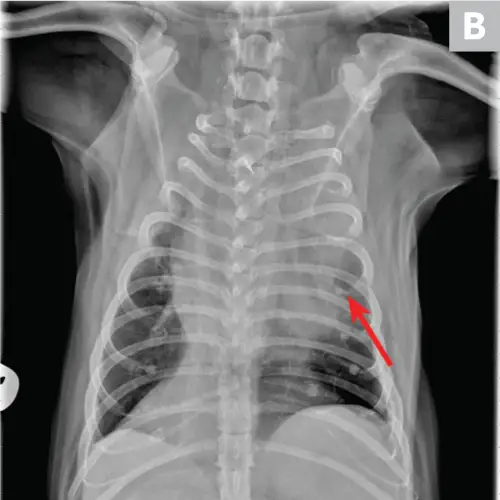

Cardiogenic edema is caused by increased hydrostatic pressure and is readily diagnosed by thoracic radiographic documentation of left-sided cardiomegaly, pulmonary venous congestion, and a patchy interstitial or alveolar pattern (frequently perihilar). Echocardiographic evaluation may support diagnosis.23 Natriuretic peptides may provide additional insight in differentiation between congestive heart failure and other causes of respiratory distress (Figure 4). Plasma B-type natriuretic peptide has been shown to have discriminatory value in dogs; however, some degree of overlap exists between groups.24

FIGURE 4A

Congestive heart failure. Note the left-sided cardiomegaly, pulmonary venous congestion, and interstitial pulmonary pattern. Edema is not exclusively perihilar.